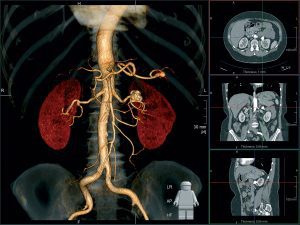

Компьютерная томография – это метод исследования, основанный на использовании рентгеновских лучей. Через специальное оборудование, называемое томографом, проходит рентгеновское излучение, которое регистрируется и преобразуется в изображение с помощью компьютера. Таким образом, врачи получают детальные снимки внутренних органов и структур человеческого тела.

Получение снимков само по себе недостаточно для определения точного диагноза. Результаты компьютерной томографии требуют расшифровки и анализа со стороны опытного врача-радиолога. Он интерпретирует полученные данные и делает заключение о наличии или отсутствии патологий, а также определяет степень их развития.

Для расшифровки результатов КТ важны навыки и опыт врача-радиолога. Профессионал способен выявить даже незначительные изменения и сделать точные выводы о здоровье пациента. Владение новейшими методами и технологиями компьютерной диагностики позволяет врачам обнаруживать заболевания на ранних стадиях и назначать эффективное лечение.